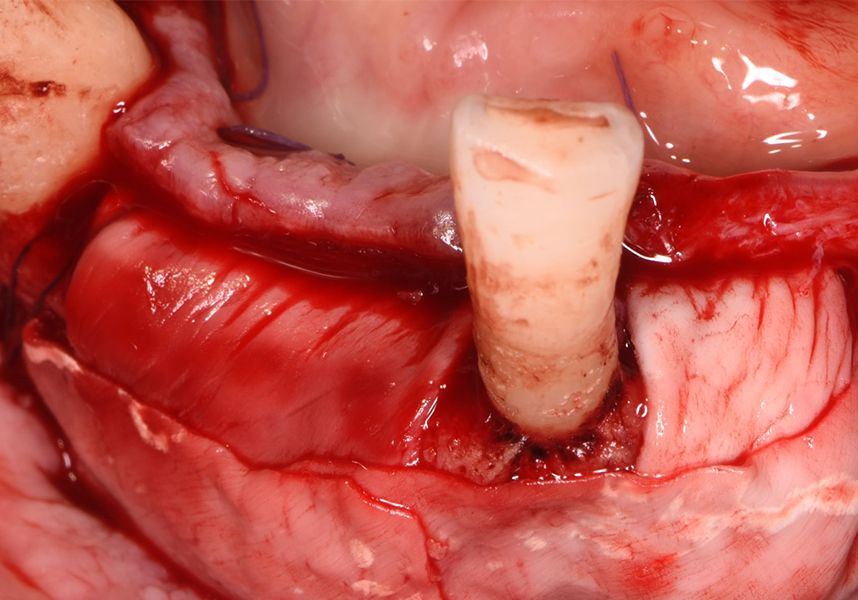

The patient was anesthetized and a flap was made from the distal area of tooth 43 up to 36. Then two Avinent Biomimetic Ocean IC implants of 3.5x10 were inserted in positions 32 and 42.

Respecting the three-dimensionally correct position of the implant led to bone fenestration, leaving the apical part of the apex of the implant exposed almost to the mid-point of its length at 42 and a third in 32.